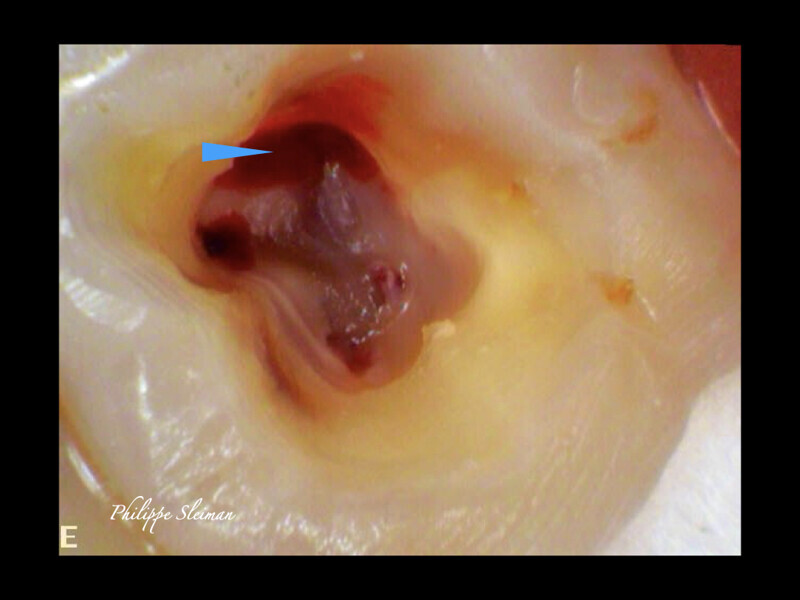

Clinical management of maxillary second molar root canal therapy in different anatomical situations